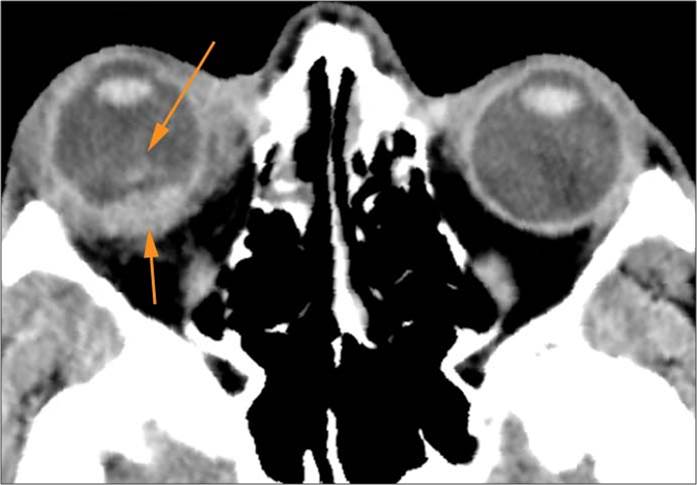

Zygomatico-orbital region and globes

There is fracture of the greater or lesser wing of the sphenoid bone, optic strut and canal, or basisphenoid, in the region of the orbital apex.

The circumferential extraconal and the intraconal orbital fat including that of the orbital apex are edematous or otherwise abnormal.

There is evidence of tension orbit.